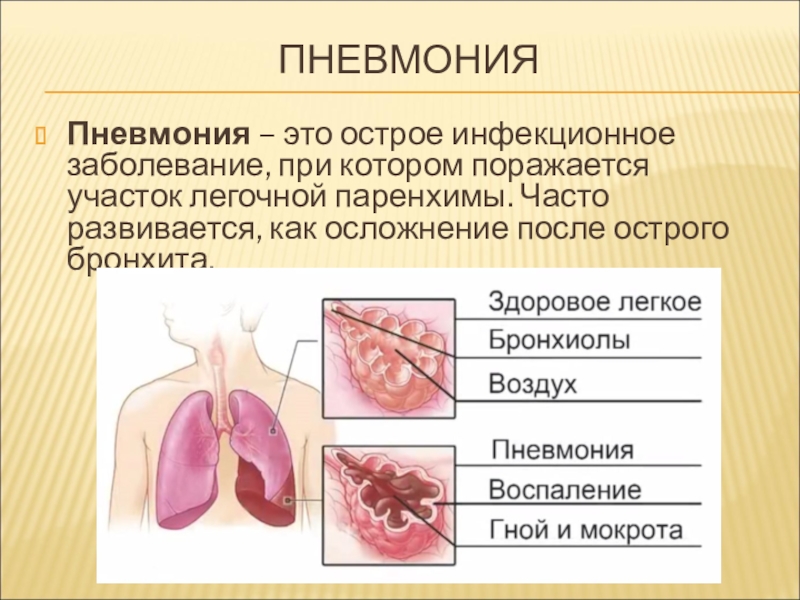

ТАСС-Досье. Пневмония (или воспаление легких) — острое респираторное инфекционное заболевание, вызывающее поражение легочной ткани. Несмотря на то, что заболевание распространено повсеместно, в наибольшей степени, по данным Всемирной организации здравоохранения (ВОЗ), от него страдают дети и семьи в странах Южной Азии и Африки (южнее пустыни Сахара).

Это происходит, когда из-за инфекции воздушные мешочки в легких (ваш врач назовет их альвеолами) наполняются жидкостью или гноем. Это может затруднить вам вдыхание кислорода, достаточного для достижения кровотока.

Пневмония — это инфекция легких, которая может быть вызвана бактериями, вирусами или грибками.Инфекция вызывает воспаление воздушных мешков (альвеол) легких и их заполнение жидкостью или гноем. Это может затруднить попадание вдыхаемого кислорода в кровоток. Симптомы пневмонии могут варьироваться от легких до тяжелых и включают кашель, жар, озноб и затрудненное дыхание.